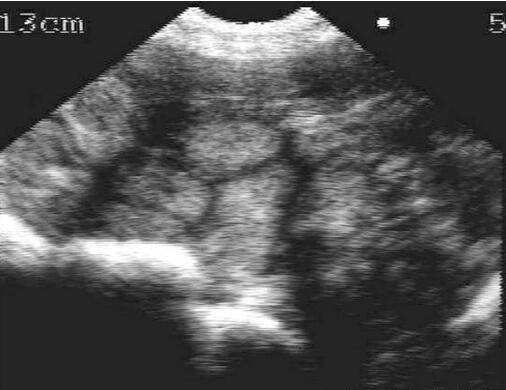

21天检测怀孕图(1/7)